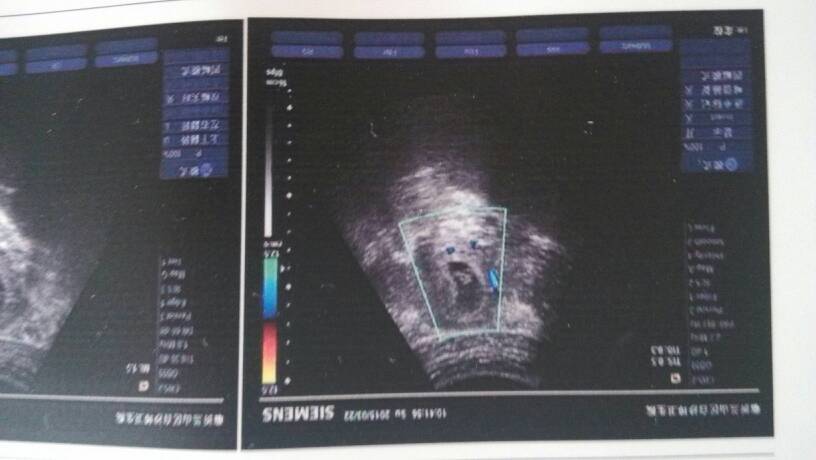

7周零4天,数据30乘以21大小妊辰囊是男孩女孩? 7周零4天,数据30乘以21大小妊辰囊是男孩女孩? 点击展开 等待_G9qi 2015-03-23 07:32 为您推荐: 其他回答 你好,现在太早,根据孕囊形状和大小不能判断是男是女,一般怀孕15周以后通过B超动态观察胎儿性别。但根据我国法律规定,是禁止通过超声检查进行非医学目地的胎儿性别鉴定。只能找个熟人问一下。 张笑珠 2015-03-23 08:14 看不出哟,这个不准的,我就是偏圆,生的儿子... 小小丫米 2015-03-23 07:58 相关问题 怀孕8w2d 妊辰囊大小4 0*5 0*1 8是男孩女孩 请问我怀孕12周零4天做B超能查准是男孩女孩吗 这是我孕19周零3天时做的B超,哪位好心人能帮我看看胎儿正常吗?能不能看出来是男孩女孩呢?真的很想